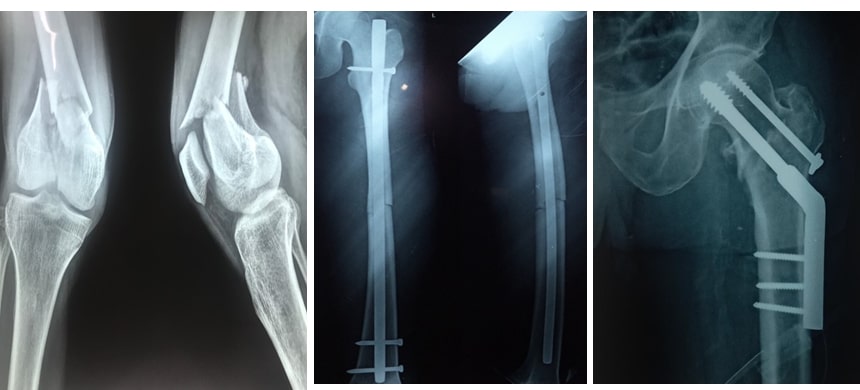

Fixing fractures using metal plates and screws has been in practice for more than 50 years. Most of the times stainless steel has been used to make this kind of plate and screws. Nowadays titanium is being used as a preferred metal for the preparation of plates, screws, nails , locking nails and elastic nails. Both these implants are very good. But titanium has got some advantages over stainless steel. Titanium is not getting rusted and is more bio compatible. Titanium will not interfere with the CT scans. But it is costly comparing with stainless steel.

These implants are fixed with the bone or strong. They don’t get dissolved by themselves. Once these fractures healed very well then there is no need for retaining those implants inside the body. They can be removed. After a few years of fracture fixation once these bones get back their strengths then we can remove them. There are some biodegradable screws and plates which will disintegrate inside our body after a certain period of times. These biodegradable implants are not very strong. And many times, they create a certain kind of allergic reaction inside our body. Many of these implants are still in the experimental stage. They are very costly too. In the future, we can expect some cheap, strong and biologically inert biodegradable implants in the market.